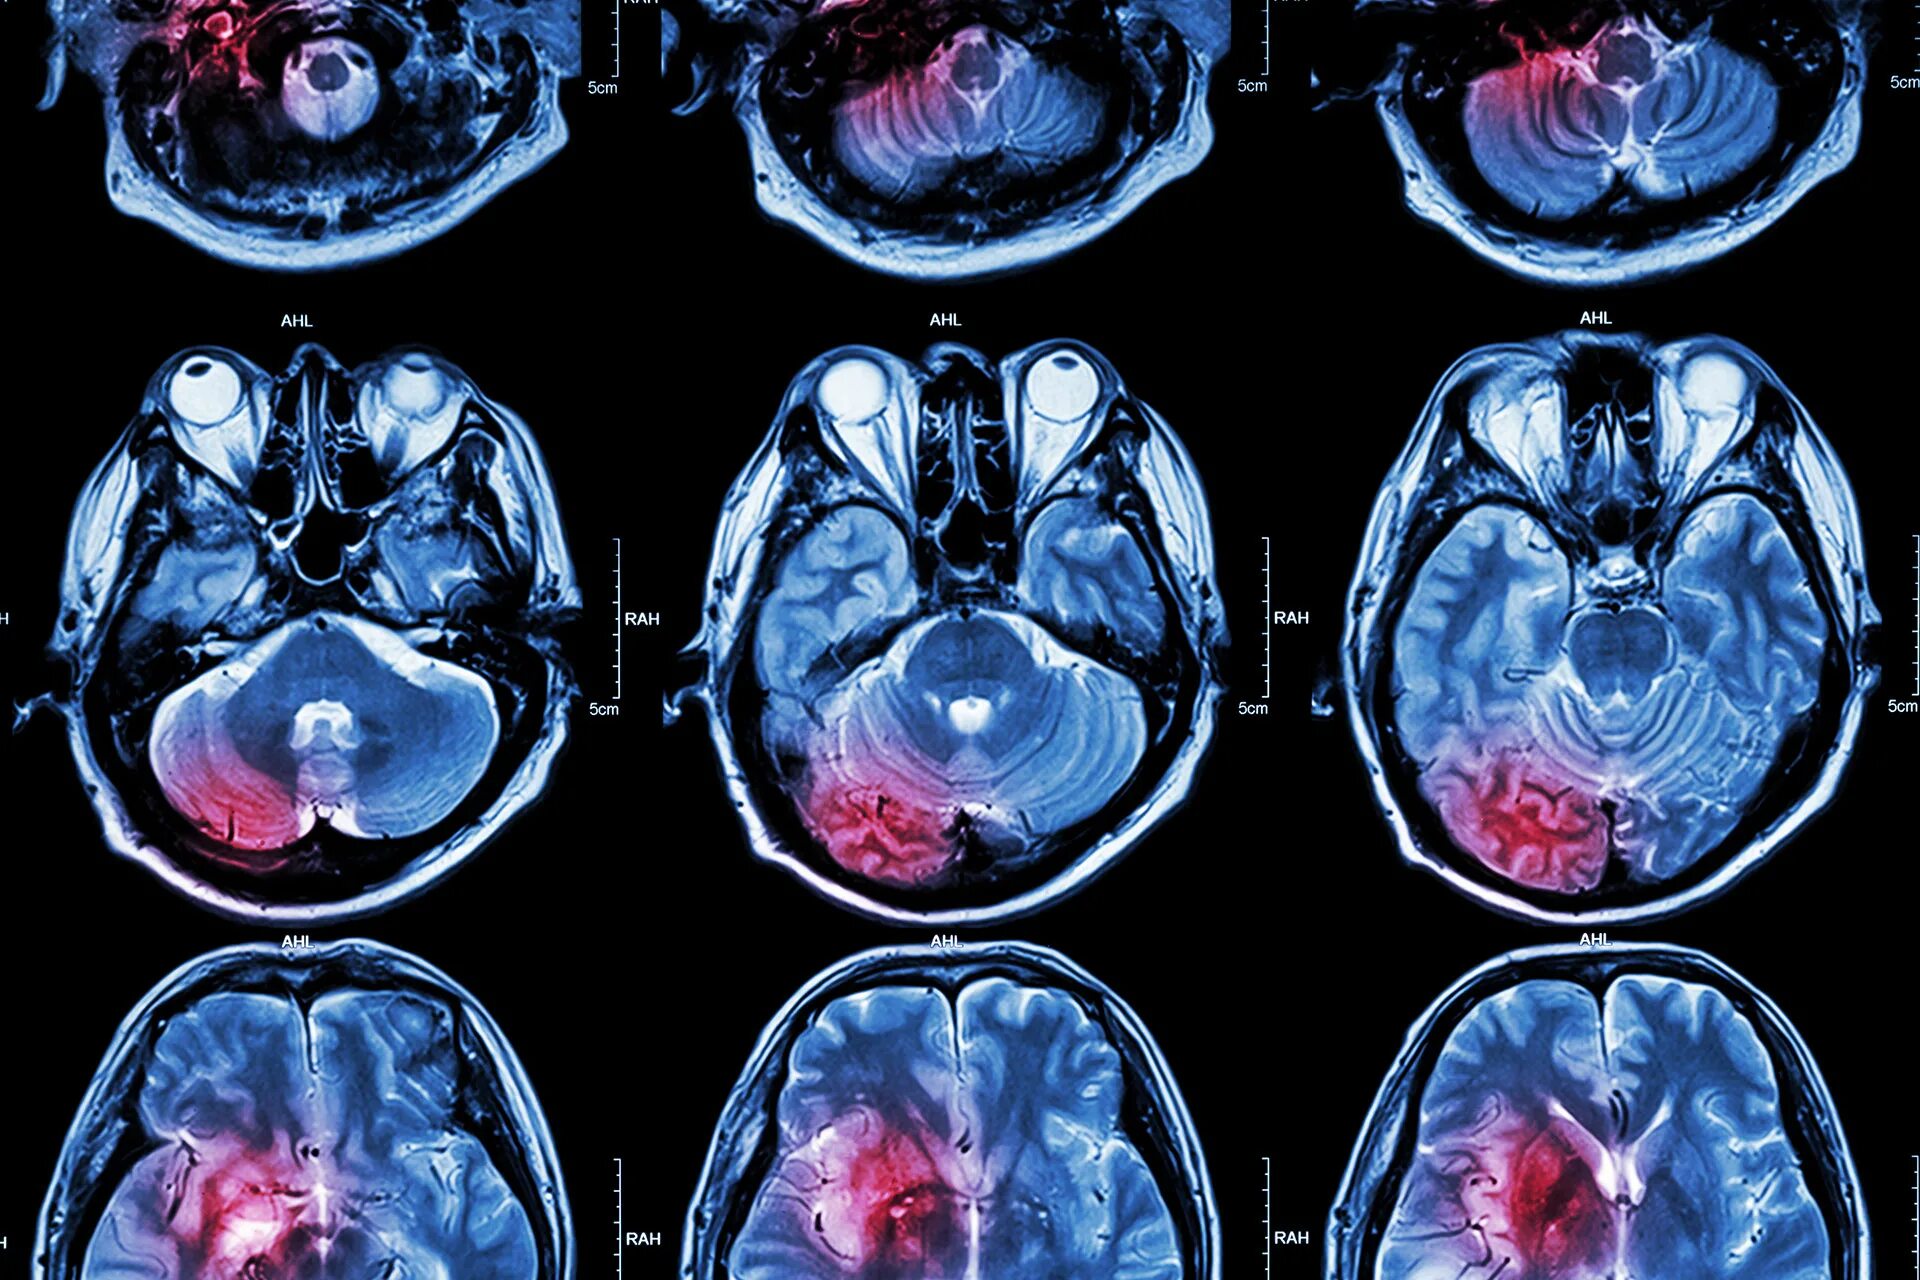

Что покажет мрт головного мозга с контрастом